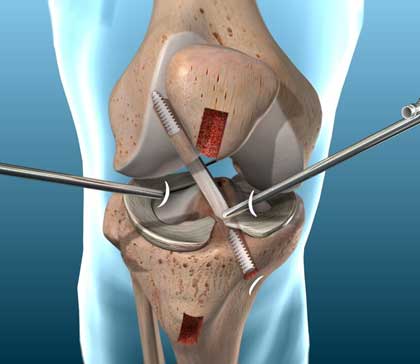

Arthroscopy (ahr-THROS-kuh-pee) is a procedure for diagnosing and treating joint problems. A surgeon inserts a narrow tube attached to a fiber-optic video camera through a small incision — about the size of a buttonhole. The view inside your joint is transmitted to a high-definition video monitor.

Arthroscopy allows the surgeon to see inside your joint without making a large incision. Surgeons can even repair some types of joint damage during arthroscopy, with pencil-thin surgical instruments inserted through additional small incisions.

Anterior cruciate ligament reconstruction (ACL reconstruction) is a surgical tissue graft replacement of the anterior cruciate ligament, located in the knee, to restore its function after an injury. The torn ligament can either be removed from the knee (most common), or preserved (where the graft is passed inside the preserved ruptured native ligament) before reconstruction through an arthroscopic procedure.

ACL repair is also a surgical option. This involves repairing the ACL by re-attaching it, instead of performing a reconstruction. Theoretical advantages of repair include faster recovery and a lack of donor site morbidity, but randomised controlled trials and long-term data regarding re-rupture rates using contemporary surgical techniques are lacking.